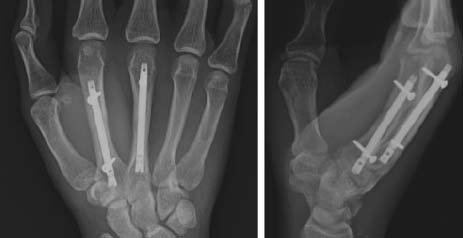

(a) 銃撃による第5中手骨骨幹部の粉砕骨折の術前X線写真。 (b) 非観血的整復および経皮的ピンニング後の術中透視像、および(c, d) 術後3週および23週のX線写真。骨折の癒合が進行し、骨のアライメントも良好である。